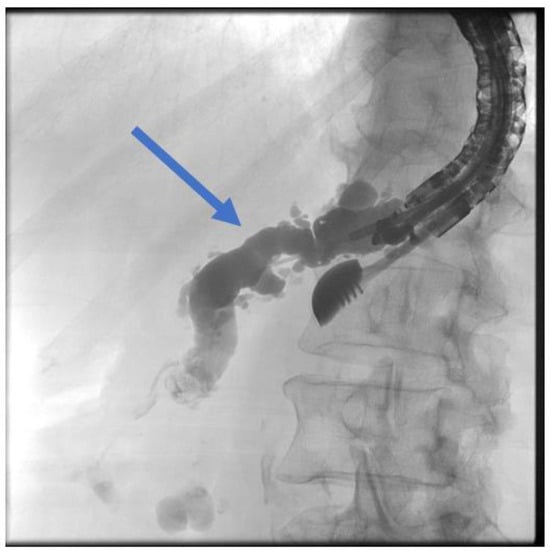

The patient is positioned prone on an X-ray fluoroscopy table and undergoes endoscopic ultrasound (EUS) using a therapeutic longitudinal scanner (e.g., EG 3270 UK, Hitachi Ultraschall, Berlin, Germany; GF-UCT 180, Olympus, Hamburg, Germany; Fuji EG-580UT2, Tokyo, Japan) following unsuccessful conventional ERP, with peri-interventional antibiotic administration i. v. (2 g ceftriaxone or 4 g tazobactam). Once the pancreatic duct is identified, a 19-G needle (Boston Scientific, Ratingen, Germany; Olympus, Hamburg, Germany) is used to puncture it in the direction of the anastomosis or papilla. Pancreatic juice is aspirated and sent for microbiological and cytological examination. Subsequently, the pancreatic duct is visualized via X-ray fluoroscopy following the instillation of the contrast medium (Figure 1 and Figure 2—selected from the clinical picture library of the reporting Dept. of Gastroenterology, Hepatology and General Internal Medicine as all the following figures).

Figure 2. Intraprocedural fluoroscopy (during EUS-guided procedure): Legend see also Figure 1.